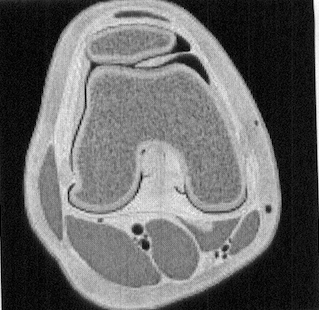

Axial graphic shows a thickened and elongated medial parapatellar plica interposed between the patella and trochlea. The plica undergoes repetitive trauma in this location. (Andrew Sonin, StatDx, retrieved August 24th, 2015)